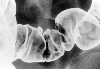

A case of cap polyposis in the rectum and sigmoid colon.

X-ray